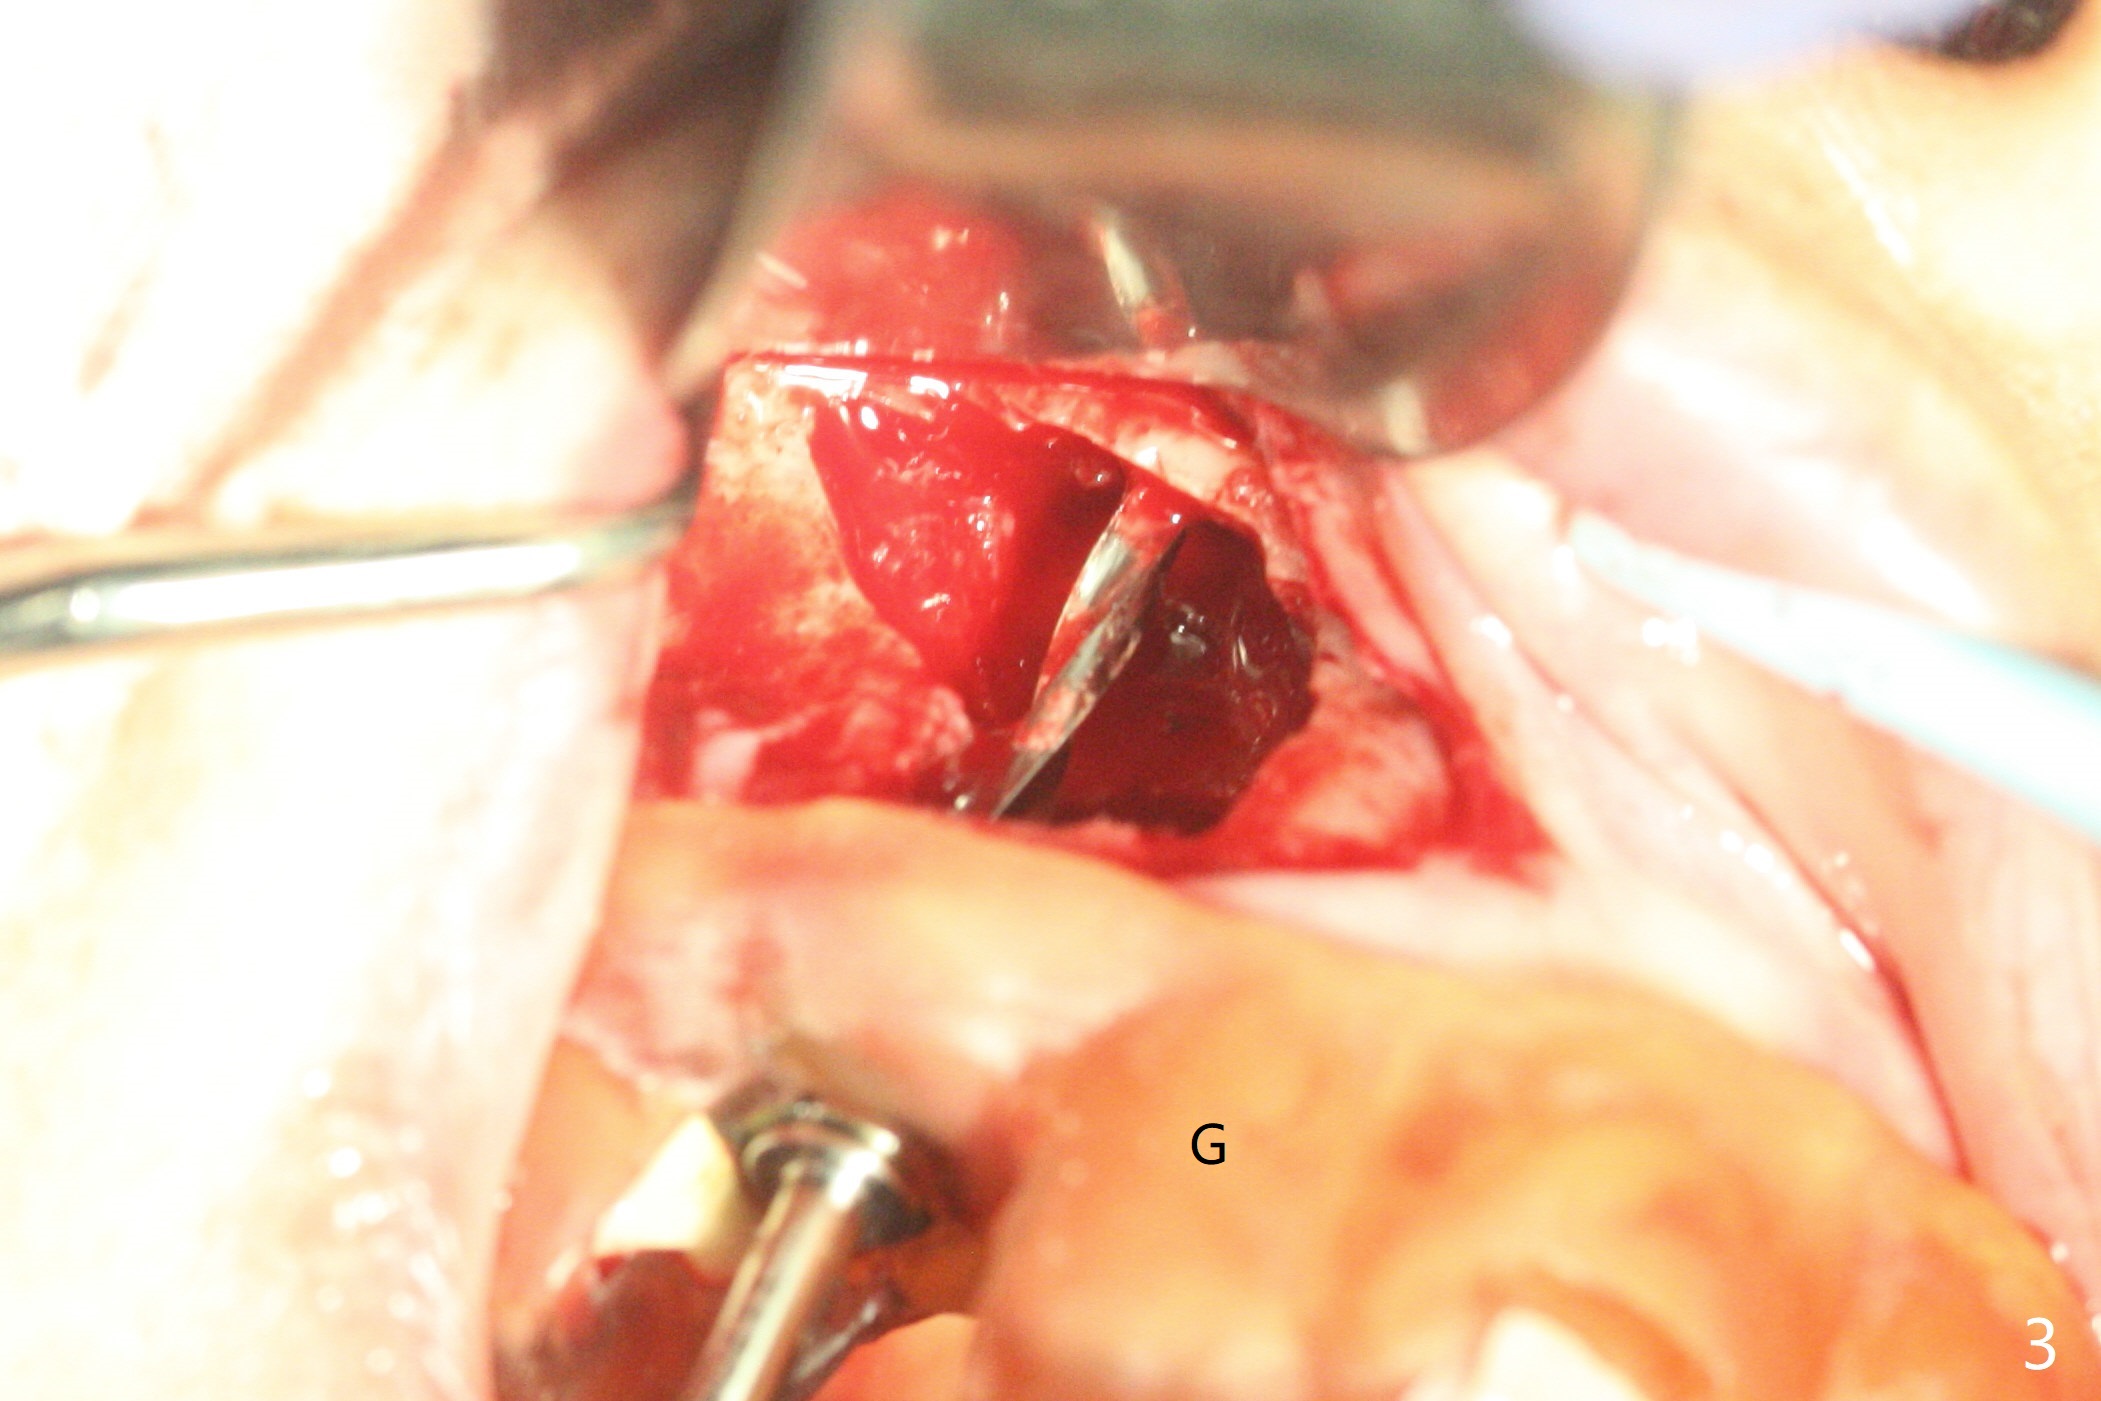

After incision and flap elevation, the crown of the impacted canine is more superficial. With removal of the buccal cortical plate and multiple sectioning of the crown, the latter is removed (Fig.1 *). Further removal of the buccal plate (P) and purchase points, the root (R) is extracted easier. In fact the apex of the root is the deepest (Fig.2). With the guide (Fig.3 G) and 2.2 mm drills, the osteotomy is established. It is pretty shallow. A 3x18 mm drill is used to deepen the osteotomy free hand (mistake: too palatal). When a 3.8x18 mm UF implant is being placed, it cannot be placed deep with the guide. When the latter is removed, the implant seems to be placed too deep and too buccal with <10 Ncm (Fig.4). A 4.5x7(5) mm abutment is placed mainly to correct the trajectory of the implant to certain degree. Placement of the implant at #3 is quite smooth (Fig.5) in spite of severe bone loss and abundant granulation tissue at #3 and 5. The implant at #5 does achieve 2 pointed fixation (Fig.4,6 arrowheads). The most coronal portion of the canine crown is left behind (Fig.6 C).